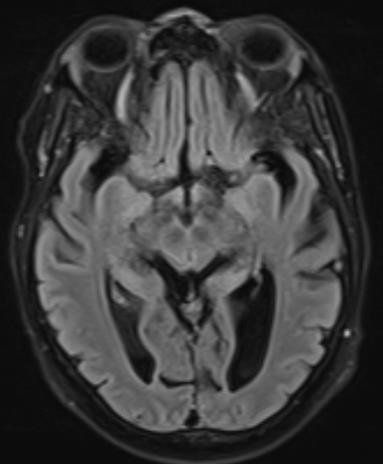

É comumente visto na RNM como áreas de aumento simétrico de sinal T2 / FLAIR envolvendo os corpos mamilares, tálamo dorsomedial, placa tectal, área periaquedutal e ao redor do terceiro ventrículo.

T2 / FLAIR: intensidade de sinal simetricamente aumentada nos:

-corpos mamilares

-tálamo dorsomedial

-placa tectal

-substância cinzenta periaquedutal

-em torno do terceiro ventrículo

T1 C + (Gd): realce de contraste também pode ser visto nas mesmas regiões, mais comumente dos corpos mamilares